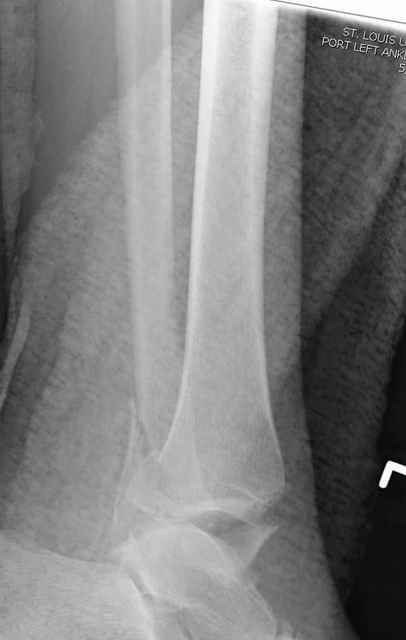

Еще, кстати, о фиксации лодыжки, если уж непременно хочется ее отдельно стабилизировать - при таком характере перелома замечательно должен сработать предложенный проф. Лазаревым с соратниками способ фиксации напряженной V-образной спицей. Опять же, открытая репозиция не нужна, мы делаем непрямую репозицию именно аппаратом. В приложении пример, там перелом малоберцовой куда менее поперечный, чем в данном случае, но все равно получилось закрыто без пластинки.

A propos fibular fixation if one is eager to stabilize it separately. In the fracture pattern a way of closed fixation by V-shaped stressed wire (advanced by colleagues from Moscow, prof. Lazarev A.F. et al.) must be excellent. We use indirect closed reduction by the external fixator. Example attached, that fibular fracture is even more suitable for plating but the wire did the job.